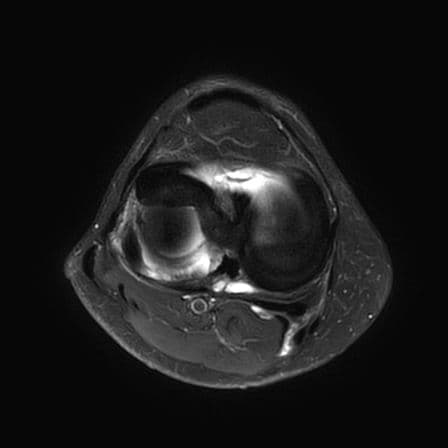

Anse de seau

MRI

Languette méniscale instable

genou

Douleurs et craquements, contexte post traumatique